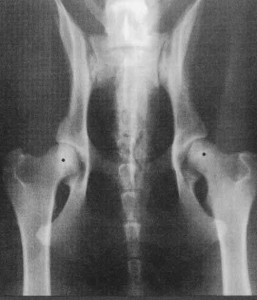

Na RTG snímku normálne vyvinutého kĺbu môžeme vidieť ideálne pologuľovitú hlavicu stehnovej kosti, uloženú z dvoch tretín v primerane veľkej kĺbovej jamke. Spodný okraj kĺbovej jamky je rovnobežný s okrajom hlavice. Kĺbová štrbina, ktorá vzniká medzi acetabulom a hlavicou kosti stehnovej je úzka.

K primárnym zmenám patrí: plytká kĺbová jamka a čiastočné až úplné vykĺbenie. V priebehu vývoja sa k nim pridávajú zmeny druhotné, ako sú: výrastky v okolí kĺbu, tvarové zmeny hlavice kosti stehnovej a iné. Aby sa dali tieto vady objektívne posúdiť a porovnávať, boli vypracované mnohé metódy na jej hodnotenie. U nás sa za základ pre posudzovanie RTG snímkov na dyspláziu bedrových kĺbov vybrala norma so smernicami FCi podľa Dr. Norbergera. Podľa nej rozoznávame: negatívny nález a štyri stupne dysplázie, od prvého ľahkého až po štvrtý, ktorý je v podstate už vykĺbenie - luxácia bedrového kĺbu.

Prvý stupeň - uloženie hlavici stehnovej kosti v acetabule je normálne, nie však ideálne; pologuľovitá, kĺbová štrbina je nepatrne širšia a na spodnom okraji kĺbovej jamky a hlavici stehnovej kosti sa nachádzajú malé tvarové zmeny.

Druhý stupeň - hlavica je nepatrne vykĺbená, nie je ideálne pologuľovitá a má náznak kužeľovitého tvaru. Kĺbová štrbina je širšia. Spodný okraj kĺbovej jamky s okrajom hlavice sa zreteľne rozbieha k pozdĺžnej osi panvy.

Tretí stupeň - ide o čiastočné vykĺbenie. Vidieť už na prvý pohľad výrazné tvarové zmeny, ako sú kužeľovitý tvar hlavice femuru a široká kĺbová štrbina. Kĺbové plochy nie sú hladké, dochádza k tvorbe kostných výrastkov. Vidieť už výrazné zmeny vznikajúce v dôsledku počínajúcej deformačnej artrózy.

Štvrtý stupeň - ide o výrazné vykĺbenie, kĺbová jamka je takmer rovná, vznikajú výrazné tvarové zmeny.